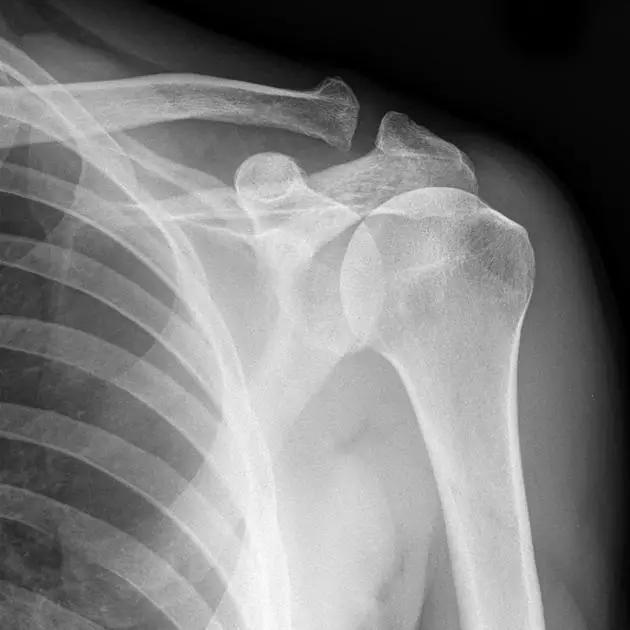

1. Hill-Sachs 损伤和反 Hill-Sachs 损伤

肩关节脱位时,肱骨头和关节盂发生撞击,肱骨头表面凹陷性骨折。

肩关节前脱位时发生的肱骨头后外侧凹陷性骨折,是经典的 Hill-Sachs 损伤(Hill-Sachs lesion);

而肩关节后脱位时发生的肱骨头前内侧凹陷性骨折,是反 Hill-Sachs 损伤(Reverse Hill-Sachs lesion/ McLaughlin lesion)。

Hill-Sachs 损伤的 X 片(来源:Hill-Sachs Injuries of the Shoulder)